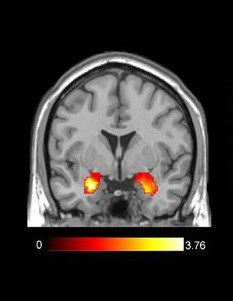

Qua fMRI, các nhà nghiên cứu đã nhìn thấy những phần não được kích hoạt khi uống các loại đồ uống khác nhau.

Hình ảnh fMRI: Khu vực được đánh dấu cho thấy hạch hạnh nhân đã được kích thích

Khi những người tham gia không biết tên của đồ uống, một trung tâm khoái cảm đặc biệt nằm ở phía trước của não được gọi là “vỏ não trước trán” (vmPFC) sẽ sáng lên. Vùng não này đặc biệt phản ứng với thức ăn mà chúng ta thấy hài lòng, chẳng hạn như đồ uống có ga có đường.

Mặt khác, khi những người tham gia biết tên đồ uống, các vùng não sáng lên liên quan đến cảm xúc và ký ức. Khi biết rằng họ đang uống Coca, những người tham gia đã thể hiện phản ứng cảm xúc khi biết tên thương hiệu, điều này dẫn đến việc họ thích Coca hơn Pepsi. Tuy nhiên, tên thương hiệu Pepsi không gây ra phản ứng này ở những người tham gia.